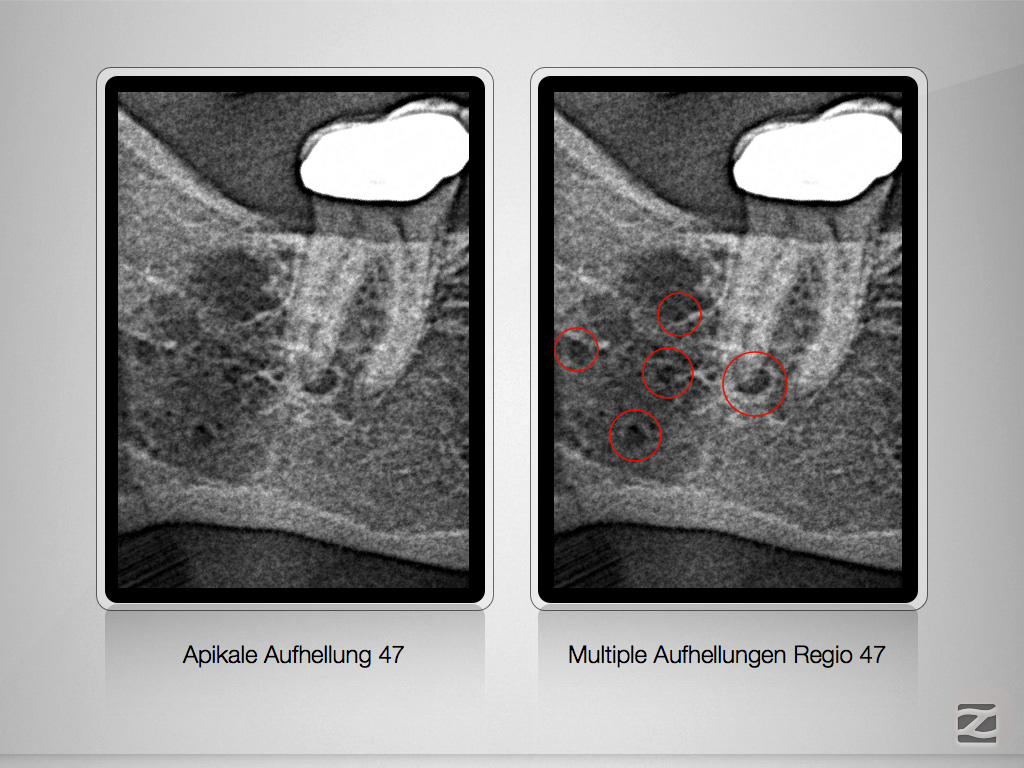

47D.002

Apikale Aufhellung